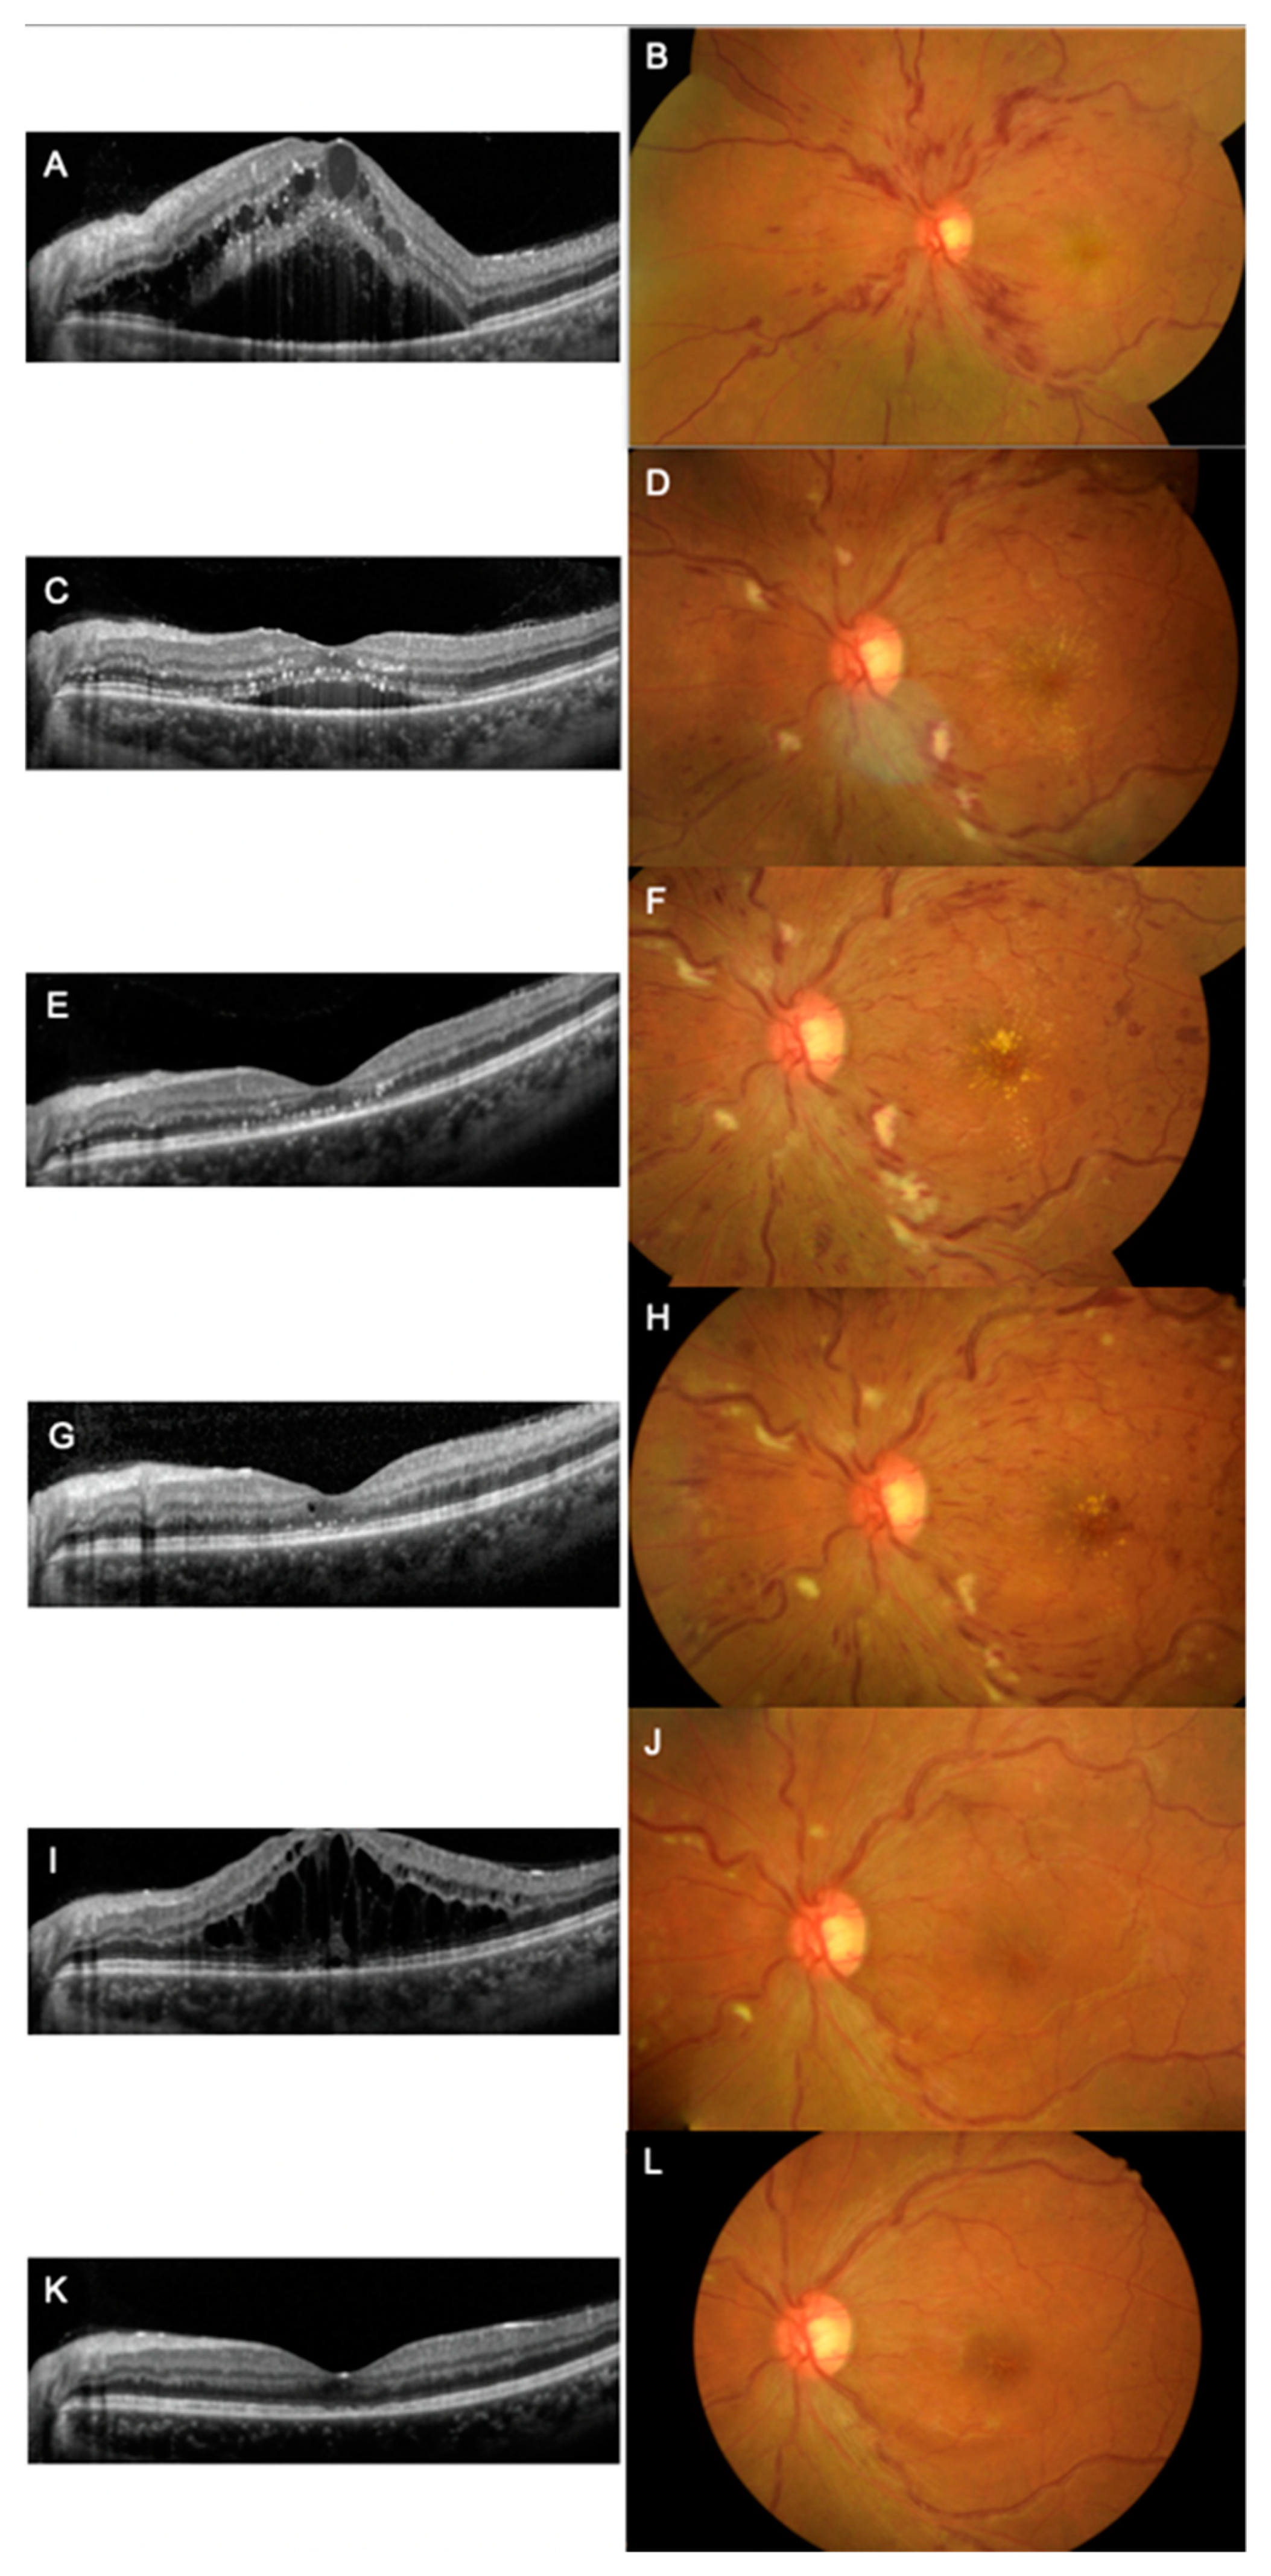

2. Case Report